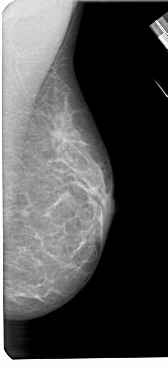

A_1419_1.RIGHT_MLO

RIGHT_MLO LINES 5491 PIXELS_PER_LINE 2506 BITS_PER_PIXEL 12 RESOLUTION 43.5 NON_OVERLAY